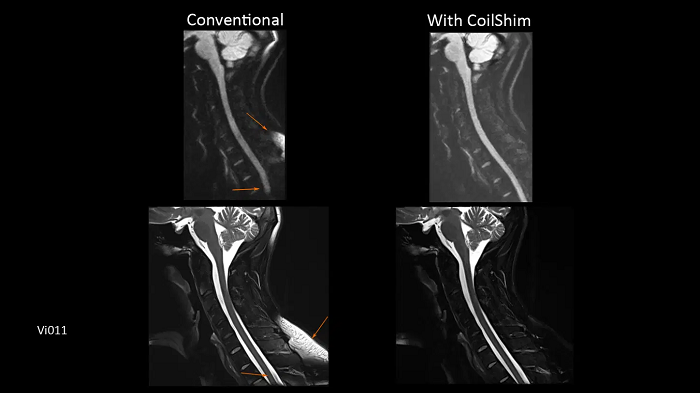

C-spine imaging with and without CoilShim

The groundbreaking CoilShim technology incorporates shim components into the new BioMatrix Head/Neck coils, enabling patient and region-specific shimming for dramatically increased fat saturation and DWI quality.

- BioMatrix Head/Neck 20 (18° tilt)

Image Credit: Siemens Healthineers